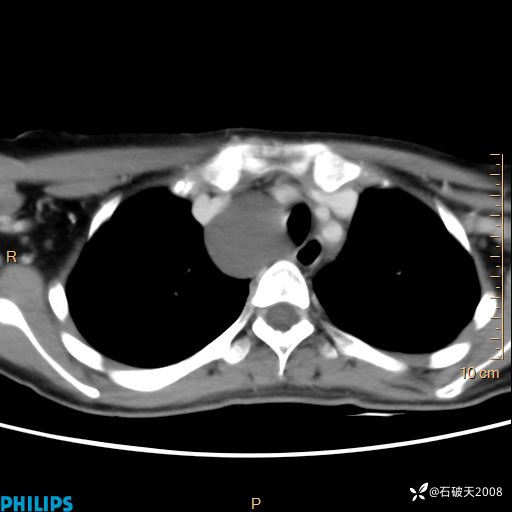

影像诊断要密切结合临床,真的很有必要(病理已公布)

女 21岁 主 诉:发现右侧颈部肿物18年余。

现病史:18年余前患者无明显诱因发现颈部偏右侧有一肿物,具体大小不明确,咳嗽、憋气时肿物增大,局部无疼痛,无吞咽不适,无胸闷及呼吸困难,至当地医院检查考虑良性病变(具体不详)并未做特殊处理,现患者自觉肿物随年龄增长而进一步变大,今日至我院行颈部CT平扫+增强提示:1.右侧颈根部、锁骨上窝及纵隔内异常密度影,考虑良性病变,淋巴管瘤?囊肿?请结合临床。2.双侧颈部小淋巴结。建议结合临床及其他相关检查。现为行进一步治疗,门诊以“颈部局部肿物”为诊断收住我科,发病来患者神志清,精神可,饮食睡眠可,大小便正常,体重无下降。

平扫